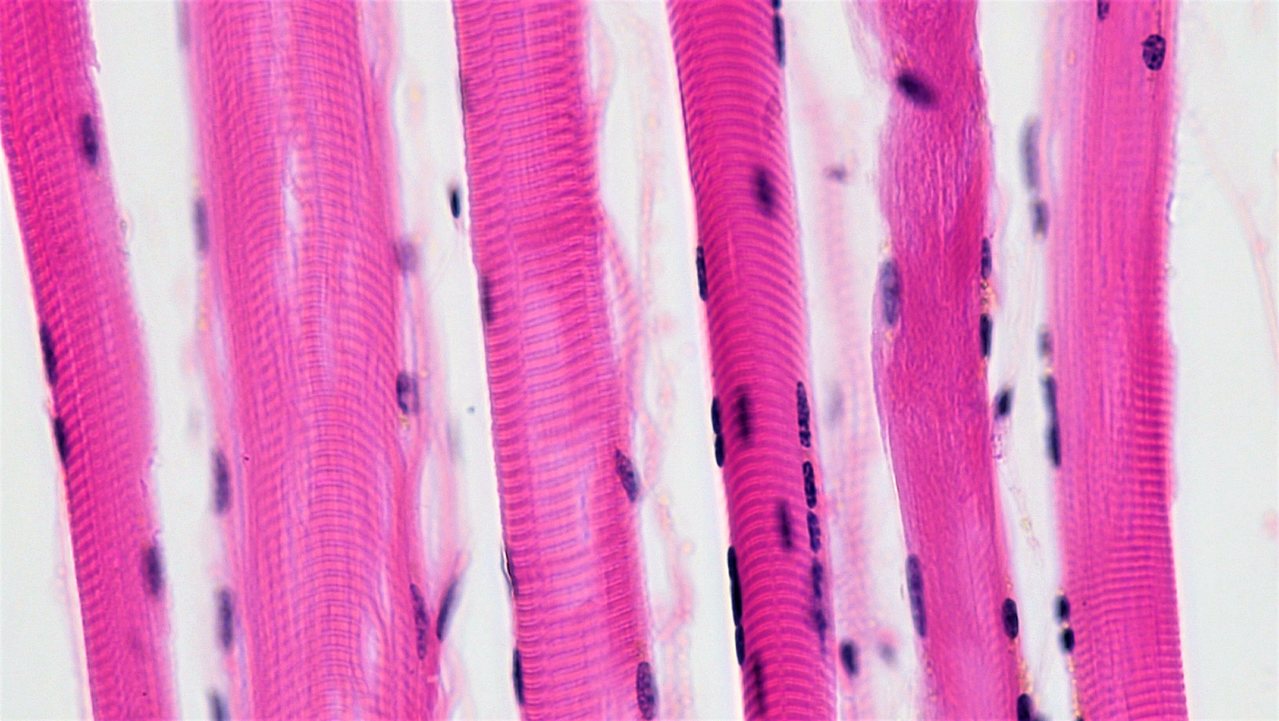

What type of muscle fibre is this? _____